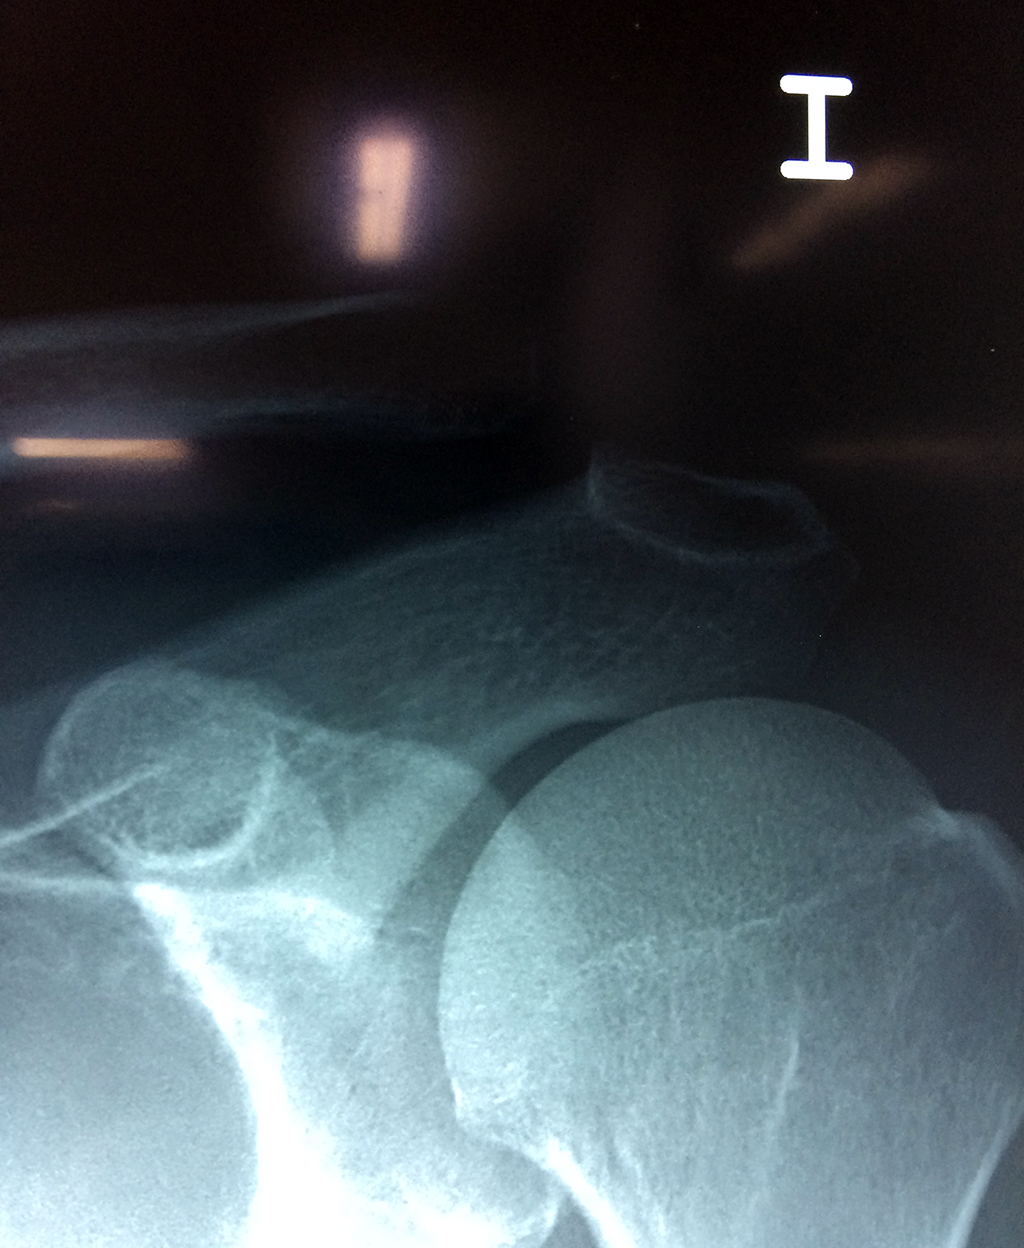

Cirugías de Húmero - Clavícula